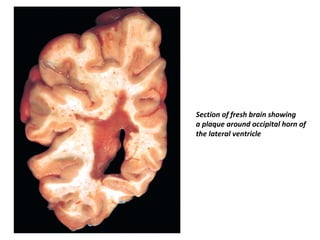

Section of fresh brain showing

a plaque around occipital horn of

the lateral ventricle